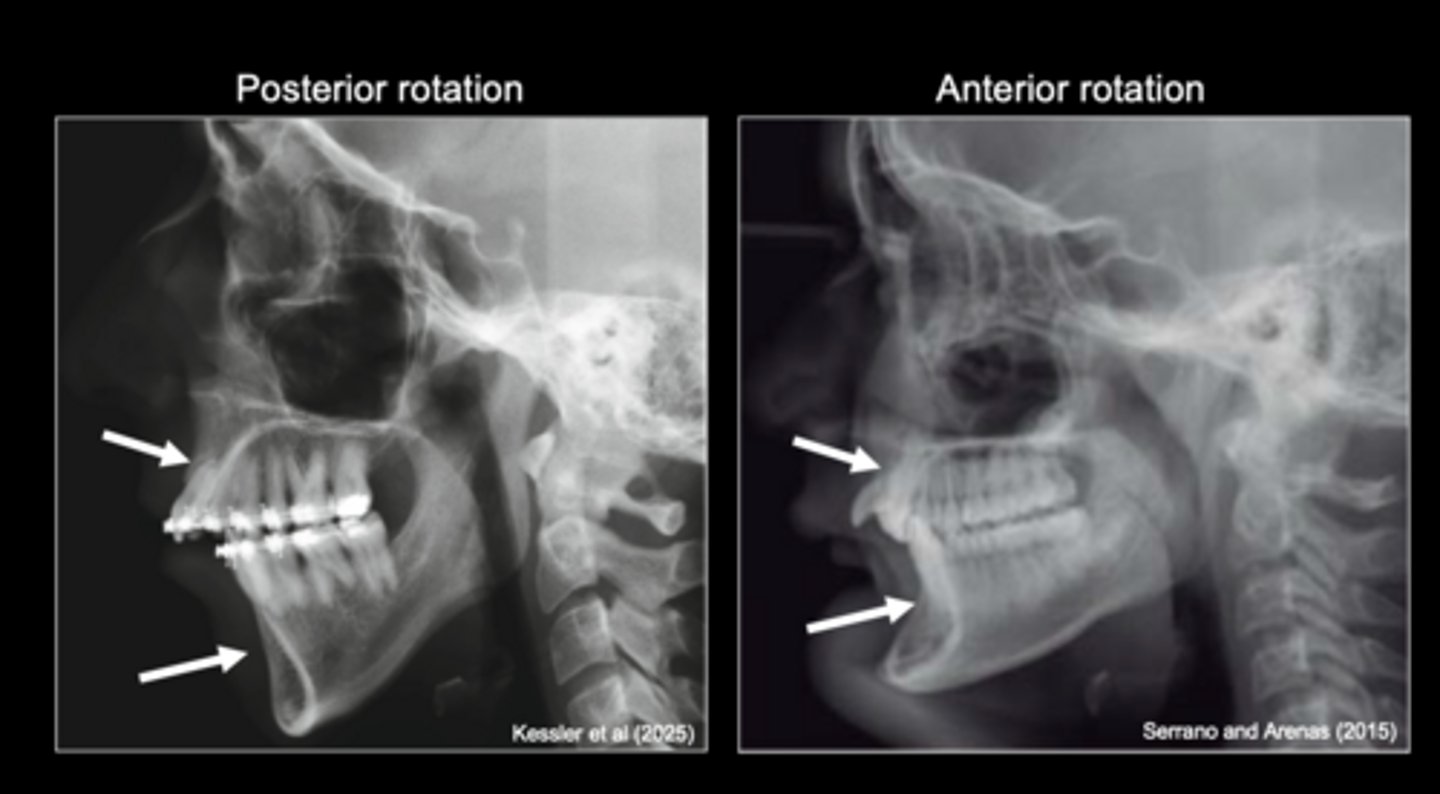

Variation in the lower face is affected by

different patterns of mandibular rotation

Variation in condylar cartilage growth results in

The potential for different patterns of mandibular rotation is evident in the

alveolar bone

Mandibular rotation produces compensatory changes in

patterns of mandibular rotation

Variation in respiratory function affects

Variation in masticatory function affects